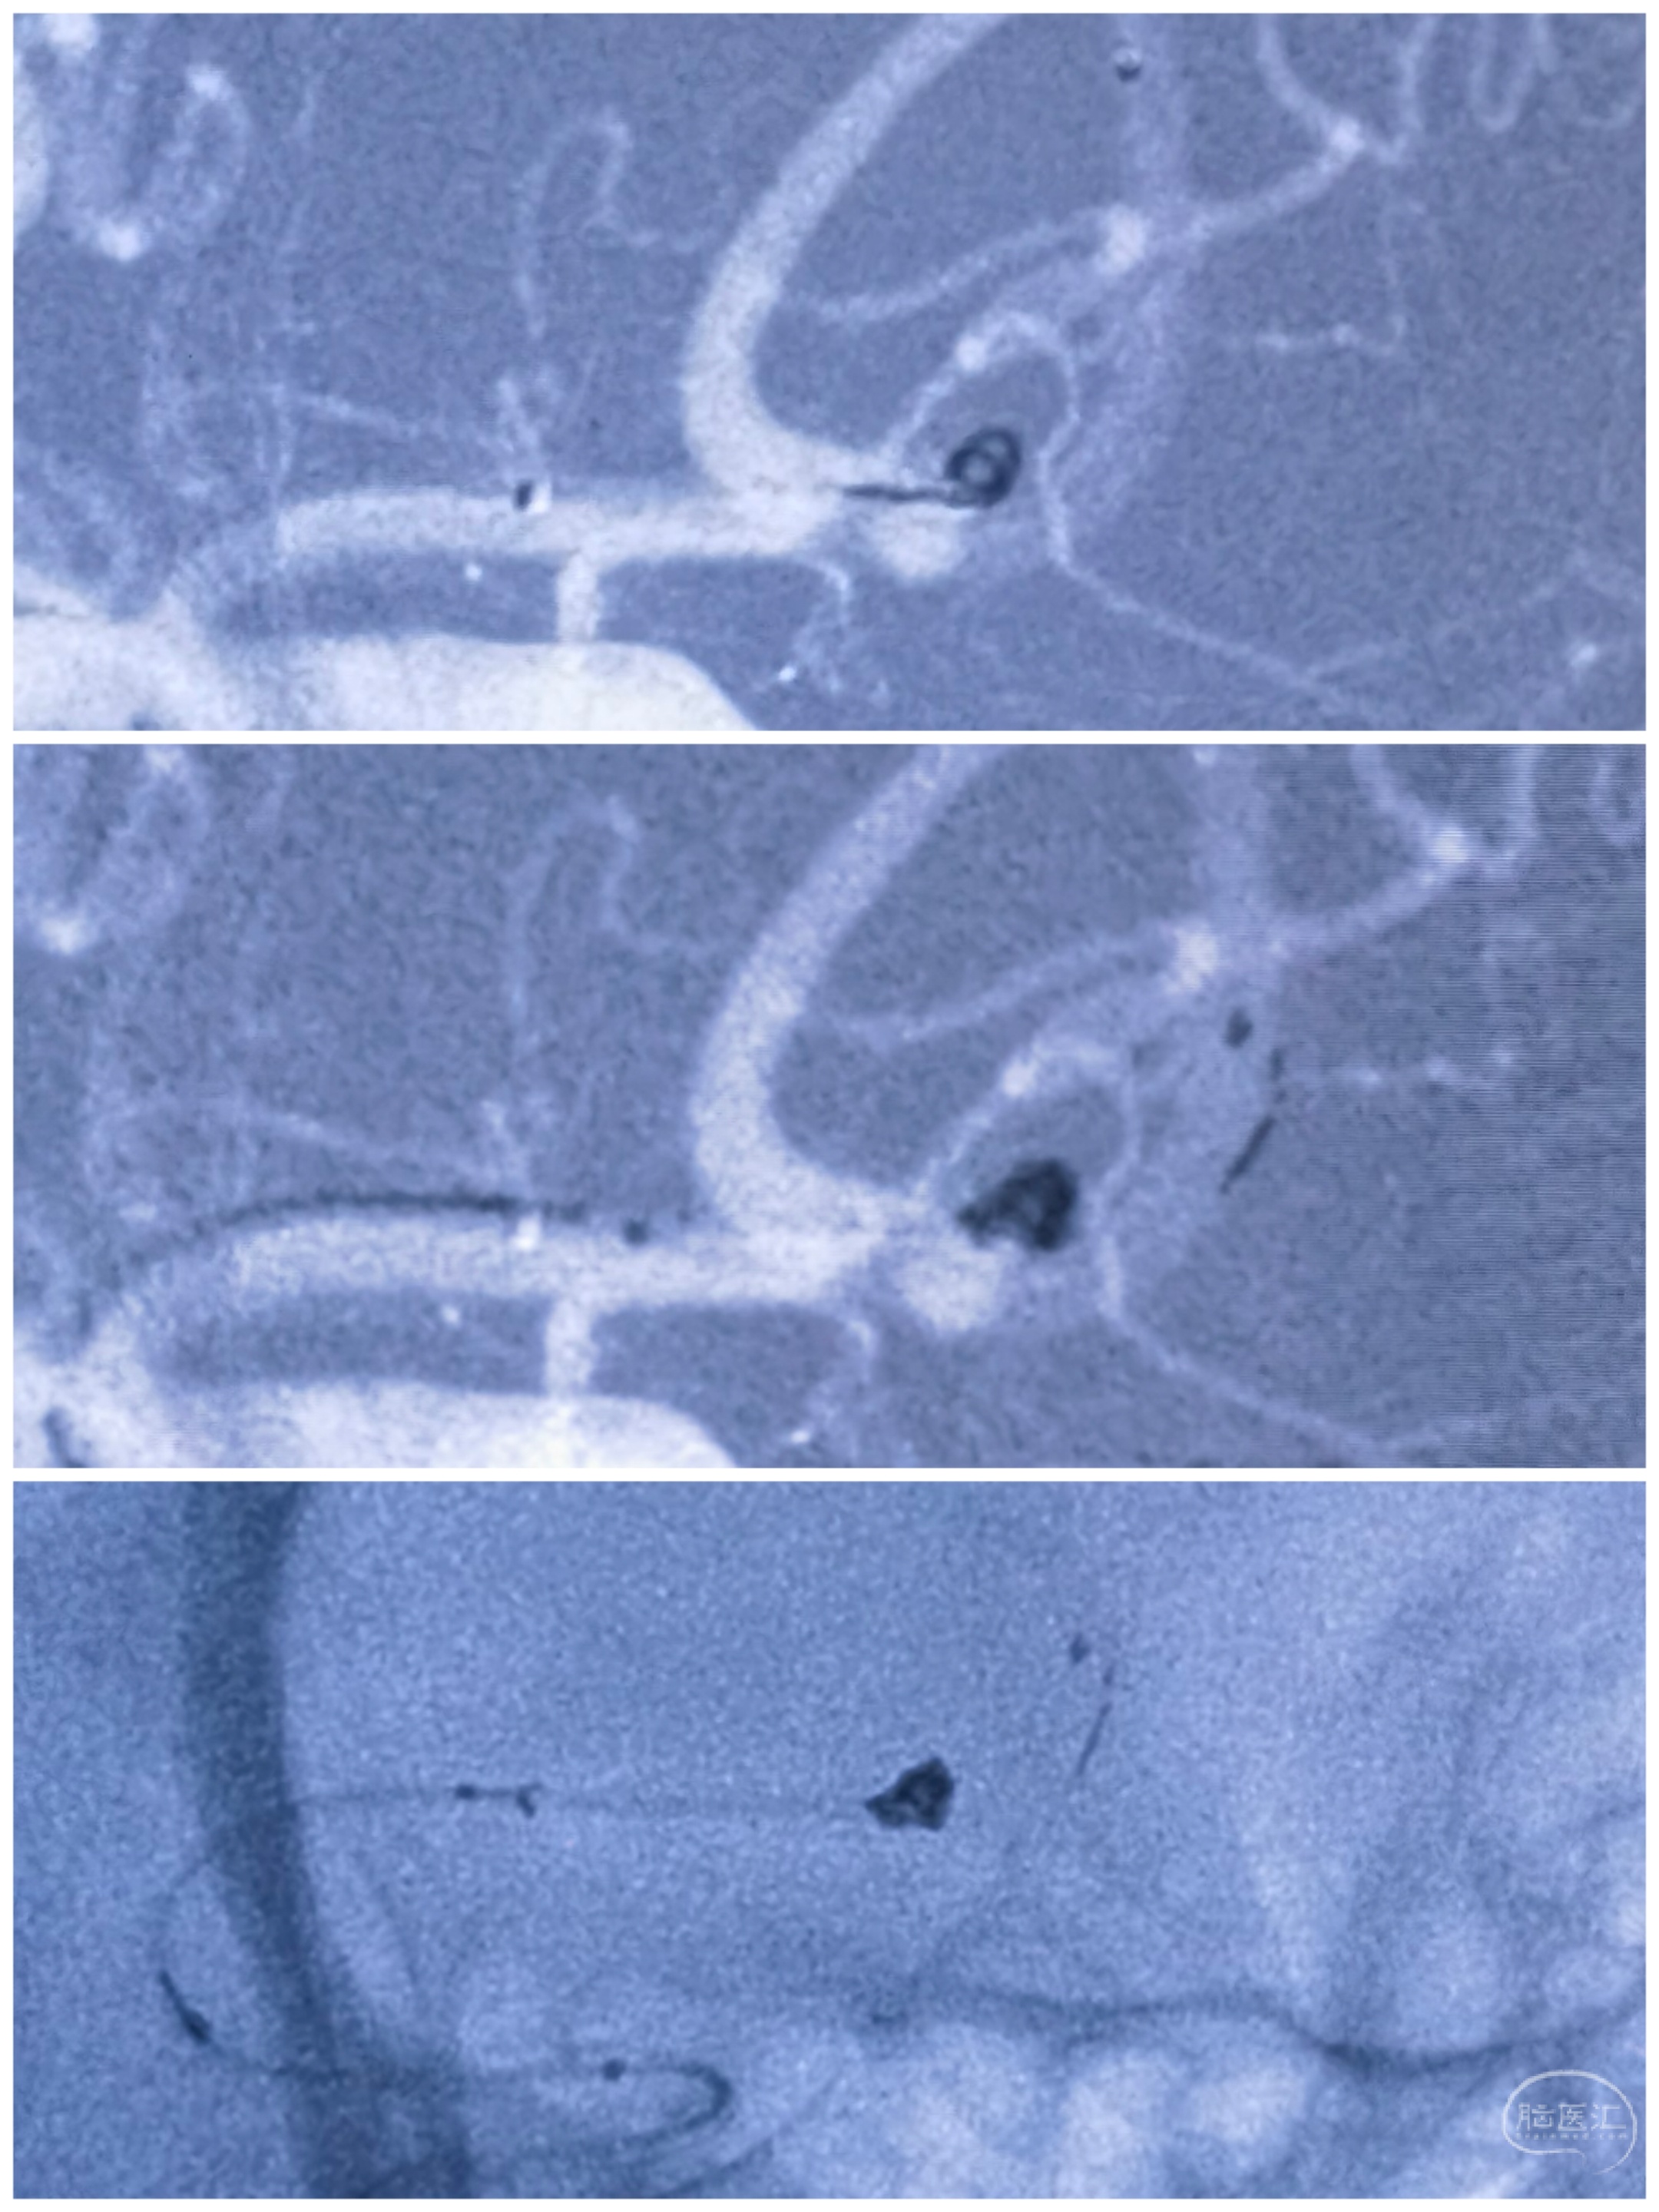

支架导管到位情况

后面顺理成章,先栓塞子囊,支架释放,后栓塞主囊

术后栓塞情况

术后左侧3D旋转造影

术后右侧3D旋转造影

术后3D重建情况:动脉瘤未显影,双侧大脑前-前交通动脉保留完好